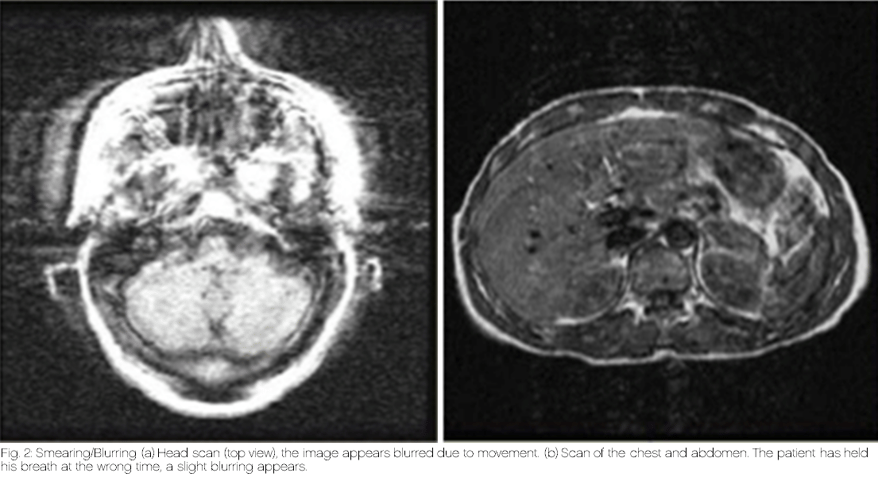

The most common motion artifacts include ghosting and smearing or blurring artifacts.

Smearing, or blurring, makes the image appear blurry or slightly out of focus.